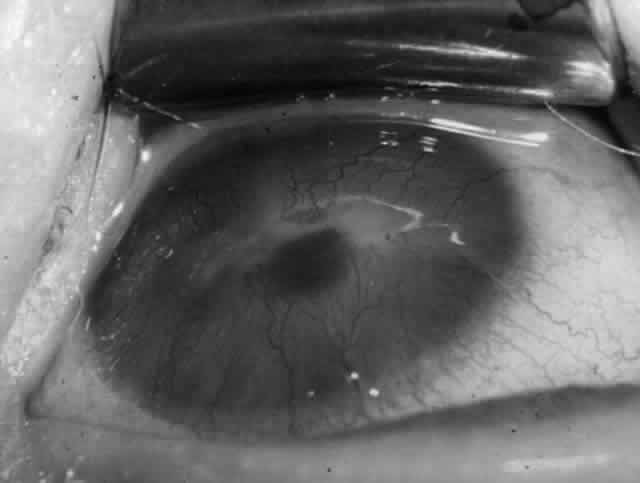

Ocular Manifestations

Clinically, the ocular disease in cicatricial pemphigoid (OCP) may present unilaterally in the form of a chronic, recurrent catarrhal conjunctivitis, but it eventually becomes bilateral. Subepithelial fibrosis is characteristic of stage 1 of OCP (Fig. 7). Stage 2 shows fornix foreshortening (Fig. 8), and symblepharon formation is the hallmark of stage 3 (Fig. 9). Stage 4, end-stage disease, is characterized by ankyloblepharon and surface keratinization (Fig. 10). Obstruction of the lacrimal ductules and meibomian gland ducts eventually produces an unstable tear film and progressive sicca syndrome, but it is to be emphasized that OCP is not a dry-eye syndrome until late in the disease course.20 Trichiasis and entropion occur because of the subepithelial fibrosis, with eventual keratopathy, corneal neovascularization, and corneal ulceration and scarring.20

Fig. 10. Stage 4 cicatricial pemphigoid. Progressive shrinkage of the conjunctiva resulted in extreme trichiasis and distichiasis and keratopathy, with compromise of meibomian ductules and lacrimal ductules and the production of a totally dry eye.